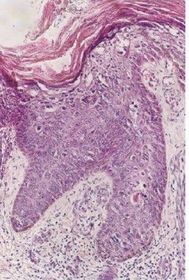

Diagnóstico e Alterações CONDILOMA ACUMINADO DO PÊNIS Hiperceratose, papilomatose, coilocitose